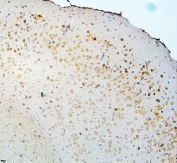

IHC staining of FFPE human glioma with DCC antibody. HIER: boil tissue sections in pH6, 10mM citrate buffer, for 20 min and allow to cool before testing.